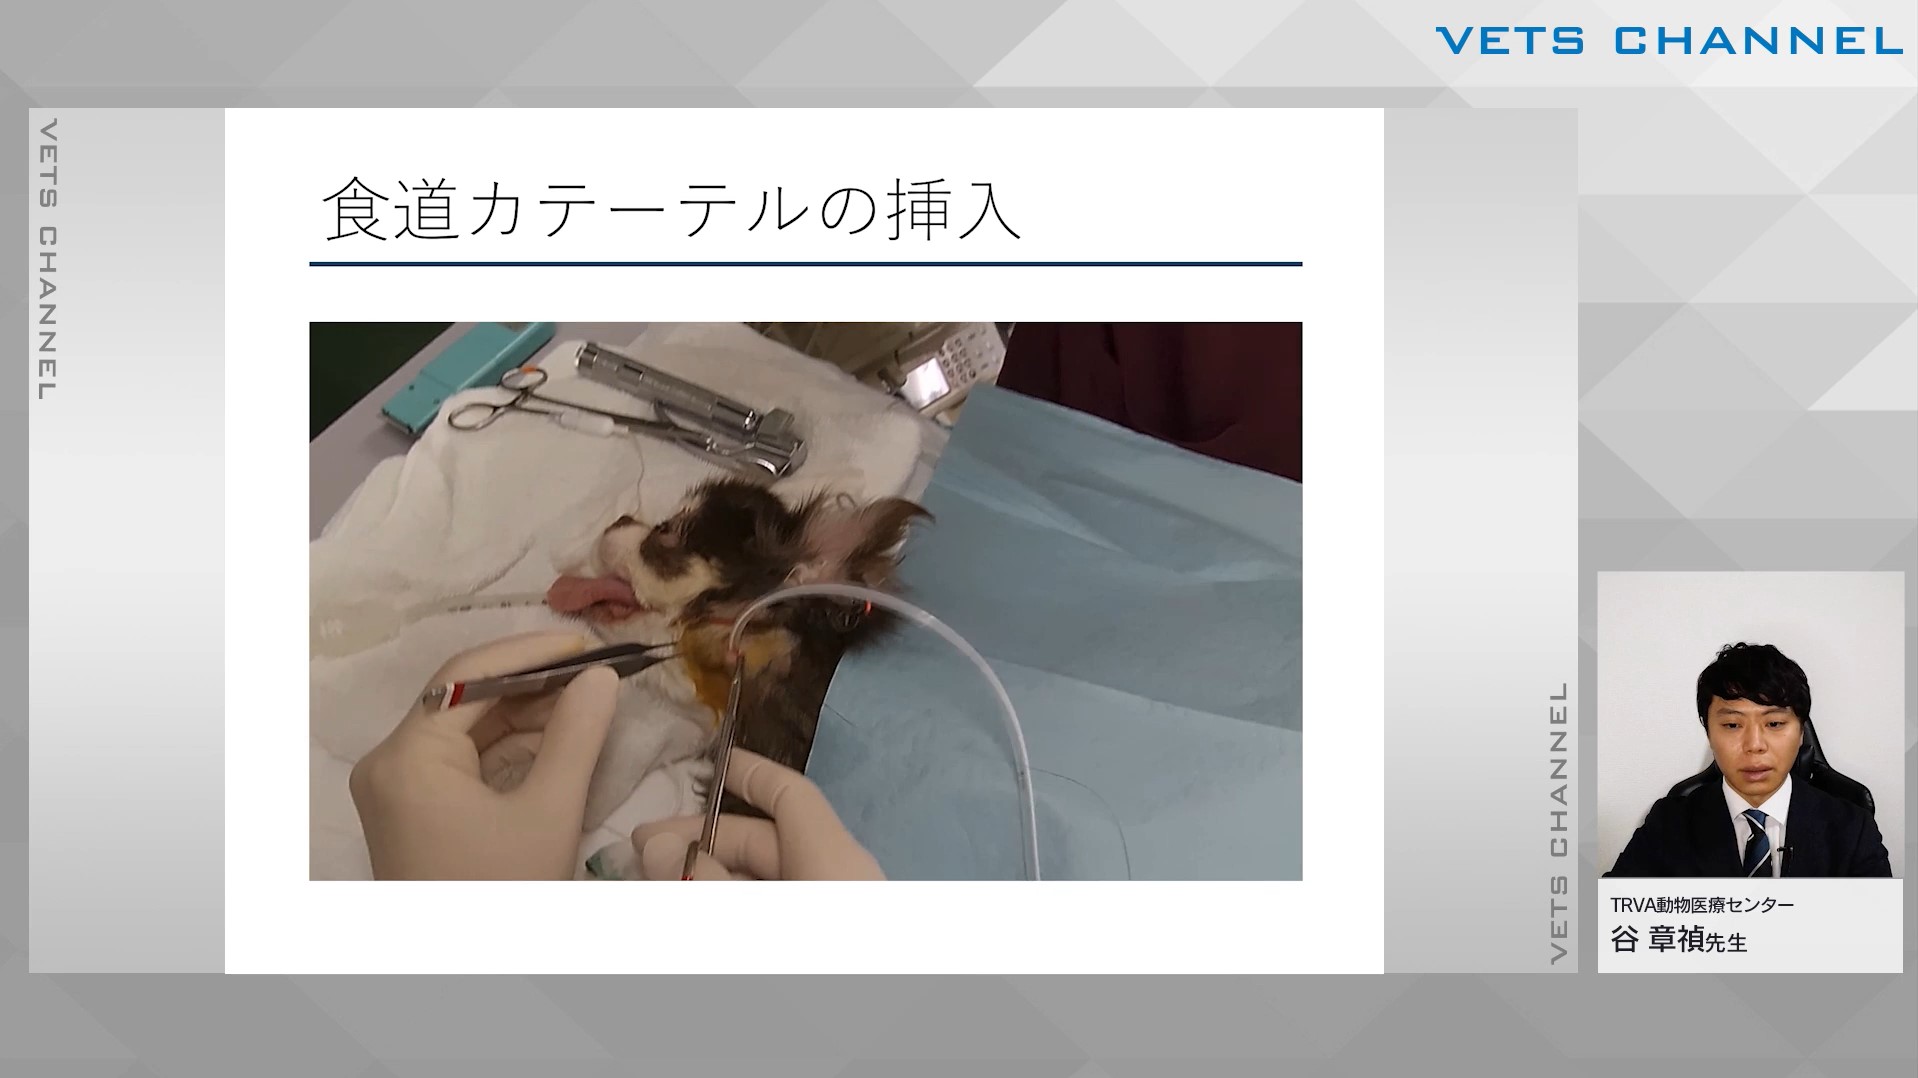

経腸栄養テクニック 経鼻・食道カテーテル

- テクニック

- 消化器科

- 腫瘍科

谷 章禎先生(TRVA動物医療センター)

22分

2024/11/22